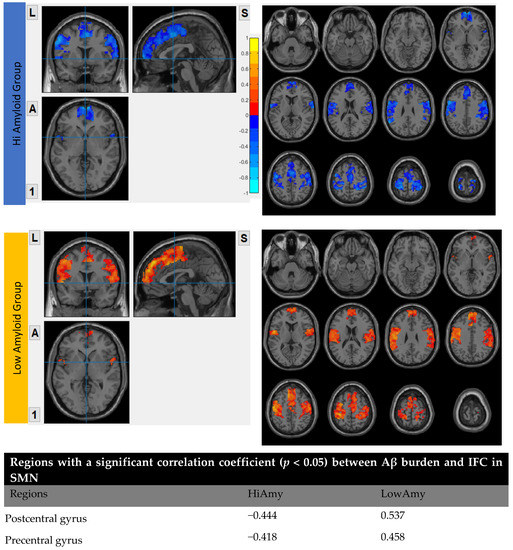

7.5. Within SMN

In the HiAmy group, voxel-wise correlation analysis showed a negative correlation (r = −0.418 to −0.493, p < 0.05) in the correlation map, indicating the Aβ accumulation relates to the reduction of functional connectivity of that region. However, in the LowAmy group, voxel-wise correlation analysis showed positive correlation (r = 0.362 to 0.612, p < 0.05) in the correlation map, indicating the Aβ accumulation relates to the increased functional connectivity of that region. Details were shown In Figure 7.

Figure 7.

Correlation between Aβ burden and IFC in SMN.